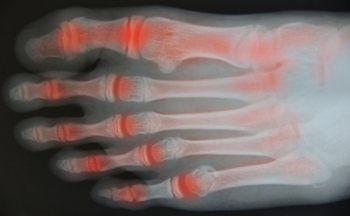

Arthritis is a joint disorder that involves the inflammation of different joints in your body, such as those in your feet. Arthritis is often caused by a degenerative joint disease and causes mild to severe pain in all affected areas. In addition to this, swelling and stiffness in the affected joints can also be a common symptom of arthritis.

In many cases, wearing ill-fitting shoes can worsen the effects and pain of arthritis. Wearing shoes that have a lower heel and extra room can help your feet feel more comfortable. In cases of rheumatoid arthritis, the arch in your foot may become problematic. Buying shoes with proper arch support that contour to your feet can help immensely.